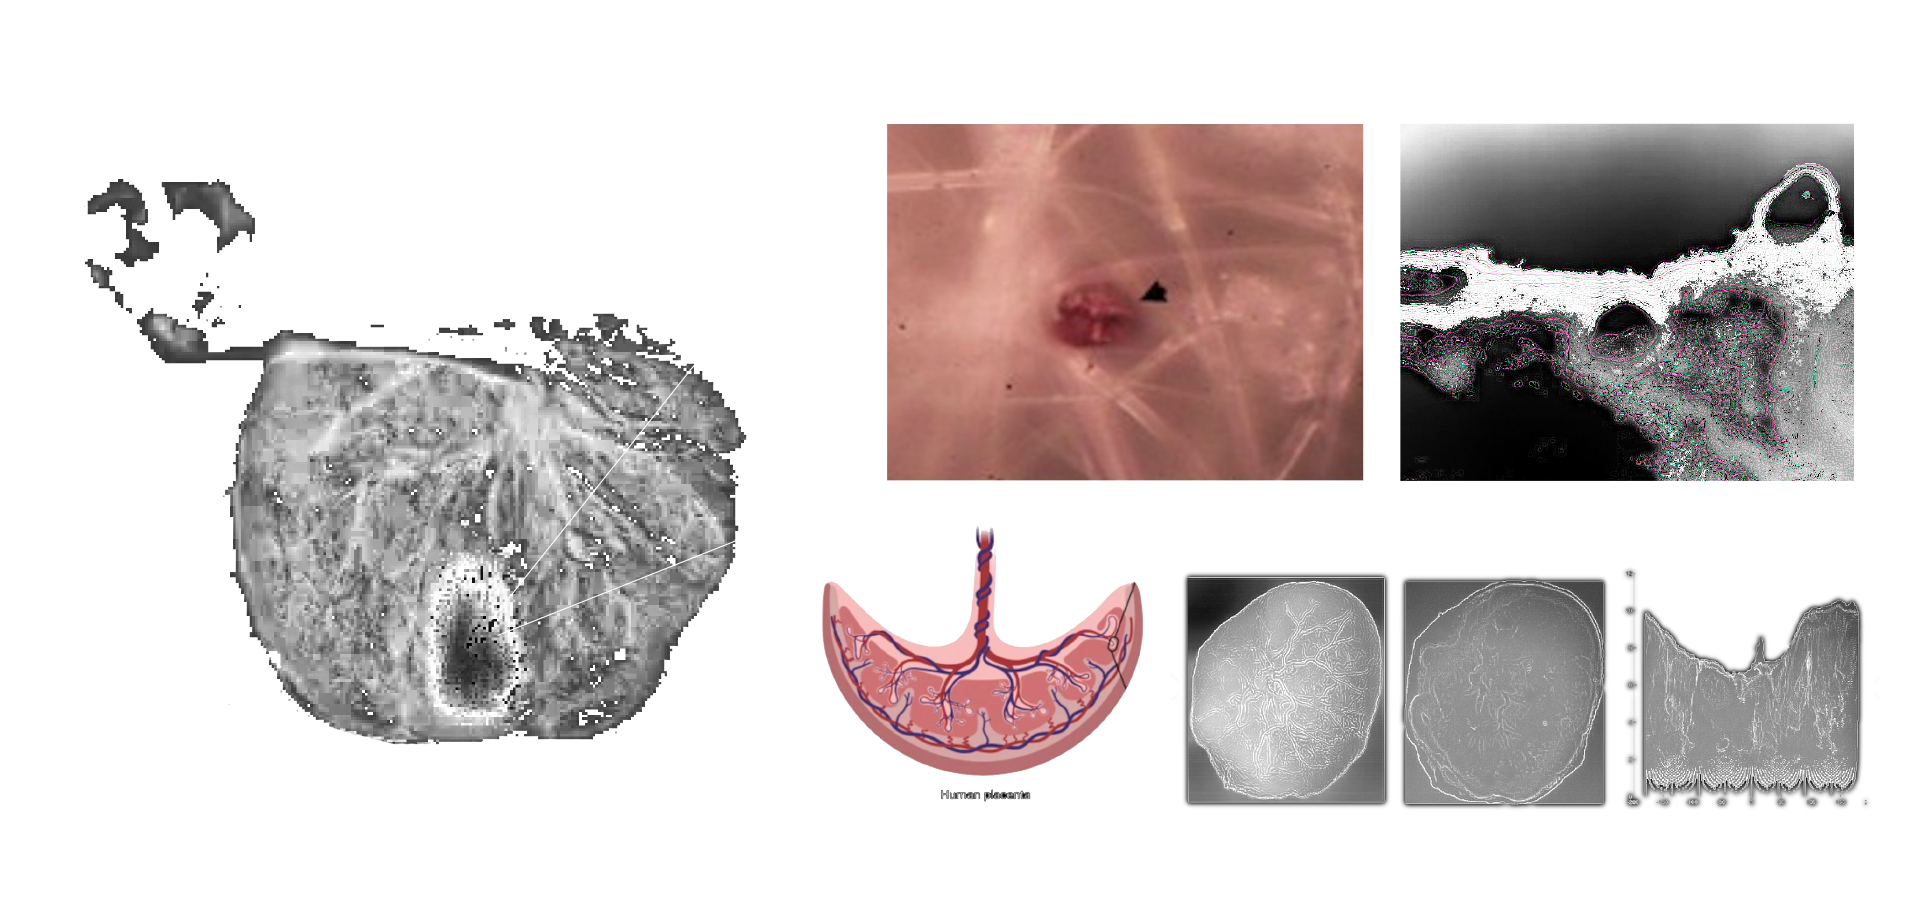

MICROPLASTICS (MPS) ARE DEFINED AS PLASTIC PARTICLES SMALLER THAN 5 MM. THEY HAVE BEEN FOUND ALMOST EVERYWHERE THEY HAVE BEEN SEARCHED FOR AND RECENT DISCOVERIES HAVE ALSO DEMONSTRATED THEIR PRESENCE IN HUMAN PLACENTA, BLOOD, MECONIUM, AND BREASTMILK, BUT THEIR LOCATION AND TOXICITY TO HUMANS HAVE NOT BEEN REPORTED TO DATE. THE AIM OF THIS STUDY WAS TWOFOLD:

1. TO LOCATE MPS WITHIN THE INTRA/EXTRACELLULAR COMPARTMENT IN HUMAN PLACENTA.

2. TO UNDERSTAND WHETHER THEIR PRESENCE AND LOCATION ARE ASSOCIATED WITH POSSIBLE STRUCTURAL CHANGES OF CELL ORGANELLES. USING VARIABLE PRESSURE SCANNING ELECTRON MICROSCOPY AND TRANSMISSION ELECTRON MICROSCOPY, MPS HAVE BEEN LOCALIZED IN TEN HUMAN PLACENTAS. IN THIS STUDY, WE DEMONSTRATED FOR THE FIRST TIME THE PRESENCE AND LOCALIZATION IN THE CELLULAR COMPARTMENT OF FRAGMENTS COMPATIBLE WITH MPS IN THE HUMAN PLACENTA AND WE HYPOTHESIZED A POSSIBLE CORRELATION BETWEEN THEIR PRESENCE AND IMPORTANT ULTRASTRUCTURAL ALTERATIONS OF SOME INTRACYTOPLASMIC ORGANELLES (MITOCHONDRIA AND ENDOPLASMIC RETICULUM). THESE ALTERATIONS HAVE NEVER BEEN REPORTED IN NORMAL HEALTHY TERM PREGNANCIES UNTIL TODAY. THEY COULD BE THE RESULT OF A PROLONGED ATTEMPT TO REMOVE AND DESTROY THE PLASTIC PARTICLES INSIDE THE PLACENTAL TISSUE. THE PRESENCE OF VIRTUALLY INDESTRUCTIBLE PARTICLES IN TERM HUMAN PLACENTA COULD CONTRIBUTE TO THE ACTIVATION OF PATHOLOGICAL TRAITS, SUCH AS OXIDATIVE STRESS, APOPTOSIS, AND INFLAMMATION, CHARACTERISTIC OF METABOLIC DISORDERS UNDERLYING OBESITY, DIABETES, AND METABOLIC SYNDROME AND PARTIALLY ACCOUNTING FOR THE RECENT EPIDEMIC OF NON-COMMUNICABLE DISEASES.